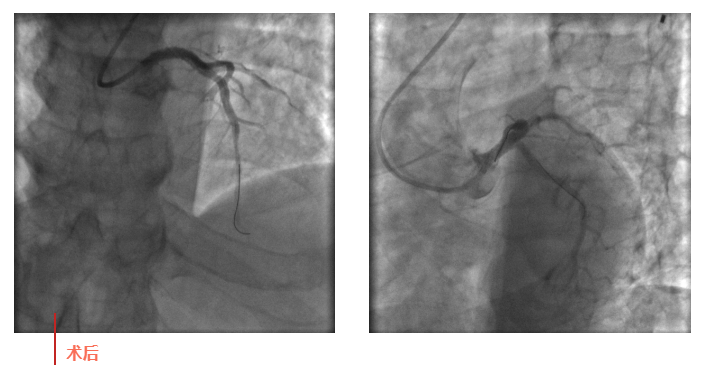

心血管內(nèi)科副主任徐先進(jìn)在主任助理農(nóng)彥林和主任汪念東的配合下行冠狀動(dòng)脈造影,結(jié)果如術(shù)前判斷一致,左主干重度狹窄,患者命懸一線。對團(tuán)隊(duì)緊急處置非常信任的李阿姨,毫無疑慮地聽取了術(shù)者的建議,同意在血管內(nèi)超聲(IVUS)的精準(zhǔn)指導(dǎo)下,在患者左主干內(nèi)植入一枚支架,成功拯救了患者的生命。

術(shù)后,患者轉(zhuǎn)入心血管內(nèi)科CCU病房,在IABP泵的支持下渡過了危險(xiǎn)期。李阿姨紅著眼眶坐在床邊,仍心有余悸,“還好有你們?。≌媸翘x謝了!”經(jīng)過心血管內(nèi)科團(tuán)隊(duì)的精心治療和護(hù)理,患者現(xiàn)已康復(fù)出院。